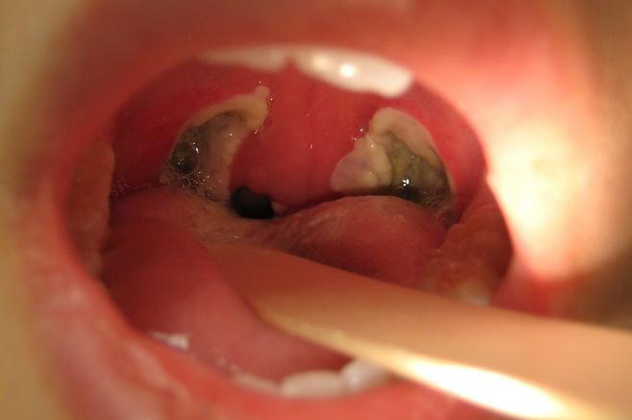

Фото

Люди делятся опытом лечения абсцесса горла, и мнения различаются. Некоторые предпочитают домашние методы: полоскание солевым раствором, травяные настои и теплые компрессы. Они считают, что такие методы уменьшают боль и отечность, способствуя заживлению. Однако многие медицинские эксперты предупреждают о рисках самолечения и его неэффективности.

При внутриротовом осмотре определяется гиперемия и значительная отечность паратонзиллярной области, увеличение миндалин, иногда они смещены в сторону. При сильной припухлости нарушается подвижность язычка и небных дужек.

- Фарингоскопия – позволяет выявить асимметрию миндалин, их покраснение, увеличение, отечность мягких тканей горла и наличие гнойного инфильтрата.